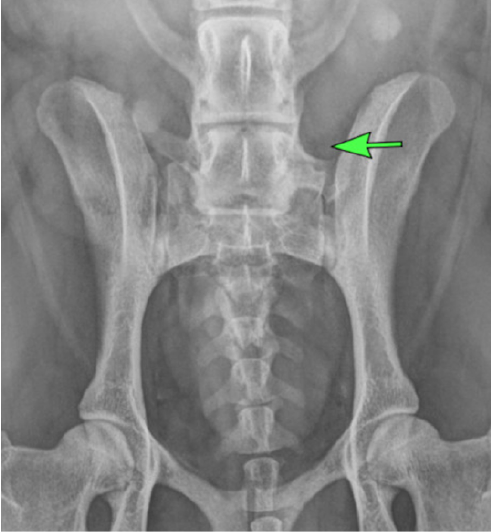

Le diagnostic se fait sur la radiographie de dépistage de la dysplasie des hanches, à condition que les trois dernières vertèbres lombaires soient bien visibles.

Ci dessous: aspect normal de L7 (Radiographie S. Mirković)

Ci dessous: aspect anormal de L7 (Radiographie S. Mirković)